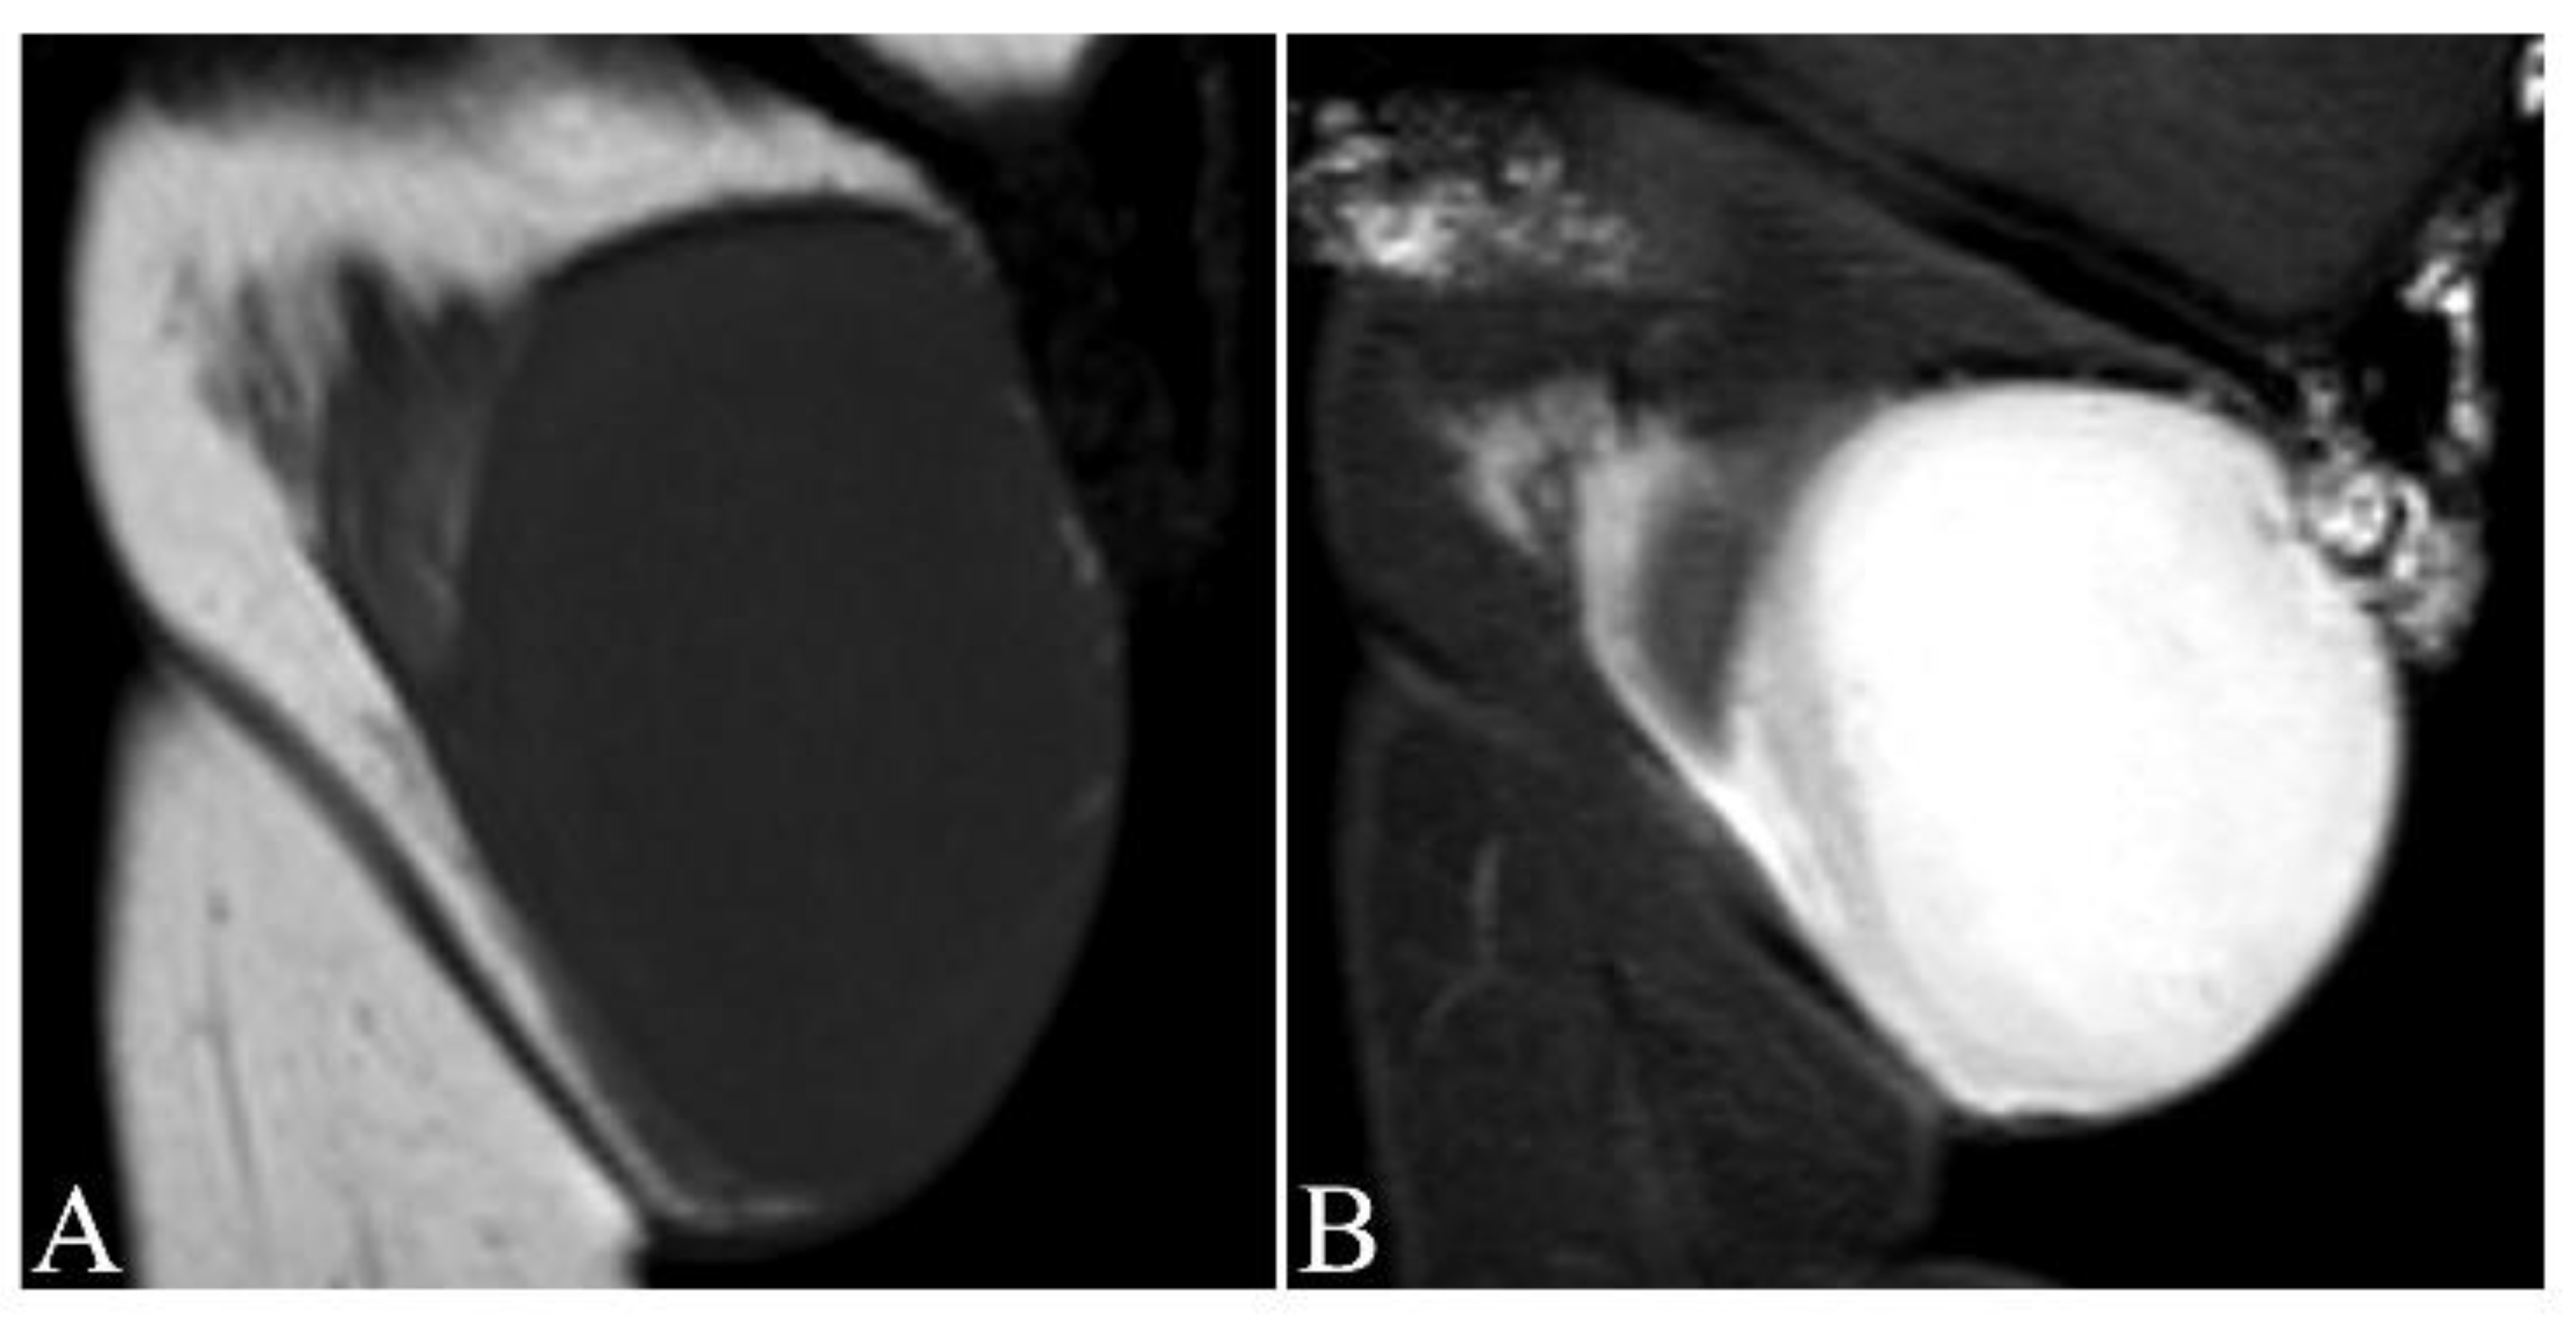

- Thornton, S.L.; Reid, J.; Papay, F.A.; Vidimos, A.T. Childhood dermatofibrosarcoma protuberans: Role of preoperative imaging. J. Am. Acad. Dermatol. 2005, 53, 76–83. [Google Scholar] [CrossRef]

- Riggs, K.; McGuigan, K.L.; Morrison, W.B.; Samie, F.H.; Humphreys, T. Role of magnetic resonance imaging in perioperative assessment of dermatofibrosarcoma protuberans. Dermatol. Surg. 2009, 35, 2036–2041. [Google Scholar] [CrossRef]

- Zhang, L.; Liu, Q.Y.; Cao, Y.; Zhong, J.S.; Zhang, W.D. Dermatofibrosarcoma Protuberans: Computed Tomography and Magnetic Resonance Imaging Findings. Medicine 2015, 94, e1001. [Google Scholar] [CrossRef]

- Torreggiani, W.C.; Al-Ismail, K.; Munk, P.L.; Nicolaou, S.; O’Connell, J.X.; Knowling, M.A. Dermatofibrosarcoma protuberans: MR imaging features. Am. J. Roentgenol. 2002, 178, 989–993. [Google Scholar] [CrossRef]

- Lee, M.H.; Kim, N.R.; Ryu, J.A. Cyst-like solid tumors of the musculoskeletal system: An analysis of ultrasound findings. Skelet. Radiol. 2010, 39, 981–986. [Google Scholar] [CrossRef]